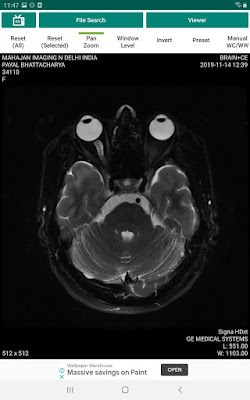

Now coming to my brain tumors.

Mother noticed continual jerkings or spasms of the left a leg and called my father, and both tried the application of pressure on the limb to calm it down but it started again. Then it was found that because of my migraines an MRI was done where a tiny spot was found which has grown over 5 times in a few years.

But the surgery was done by a doctor not aware of several facts and within 60 months I ended up with tumours scattered all over my brain.

I was diagnosed with leptomeningeal hemangioblastomas after the cyber knife in 2013.

A Ga-DOTANOC PET-CT based SSTR imaging because VHL syndrome associated hemangioblastomas frequently express SSTR ( Somatostatin receptors) confirmed that the tumours in my brain are hemangioblastomas. With this, the true nature could be seen and the diagnosis was confirmed.

I was diagnosed with supranational leptomeningeal hemangioblastomas in 2013. I have been seeking anyone experiencing the same condition but didn't find anyone till now. So I consider myself a myth, a unicorn, butterfly.